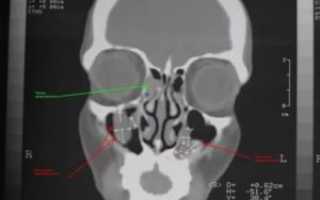

КТ пазух носа или компьютерная томография — неинвазивное информативное исследование, которое позволяет определить состояние тканей послойно.

КТ помогает врачу оценить:

- контуры,

- структуру,

- объём,

- минерализацию и плотность новообразований.

Исследование неоценимо при определении эффективности медикаментозной терапии на фоне хронических заболеваний носа.

Единственный недостаток метода — дороговизна. Альтернативной компьютерной томографии является процедура МРТ.

- Магнитно-резонансная или компьютерная томография дает полную картину патологии. Врач может увидеть, где расположено основание образования, а также оценить состояние пазух. Отличить полип от кисты. Отметить присутствие гайморита и прочих синуситов, а также закупорку соустьев.

- Рентгенография более доступная аппаратная диагностика. С использованием контраста можно оценить состояние слизистой гайморовой полости, наличие полипа.

- компьютерная или магниторезонансная томография.